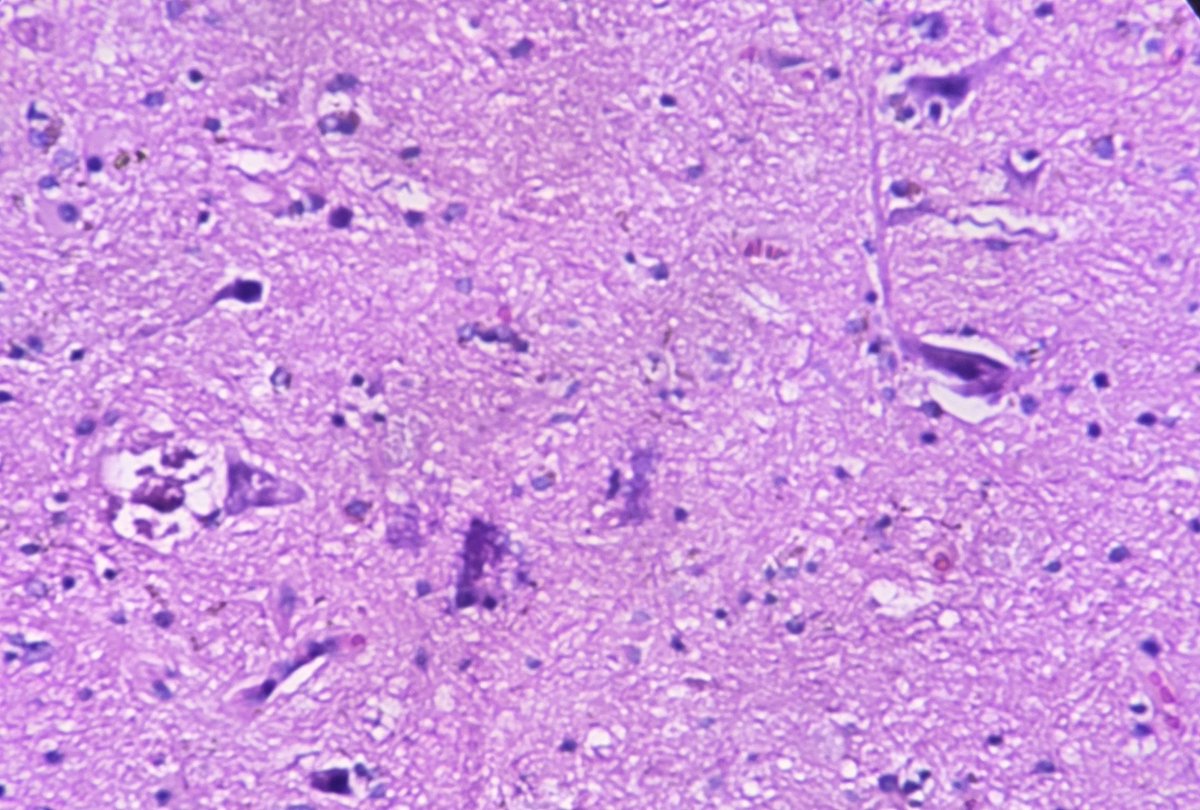

13 yrs old boy with gradually enlarging cervical lymphadenopathy. A case of metastatic lymphoepithelial carcinoma lurking in nasopharynx. #pathology #ENTPath